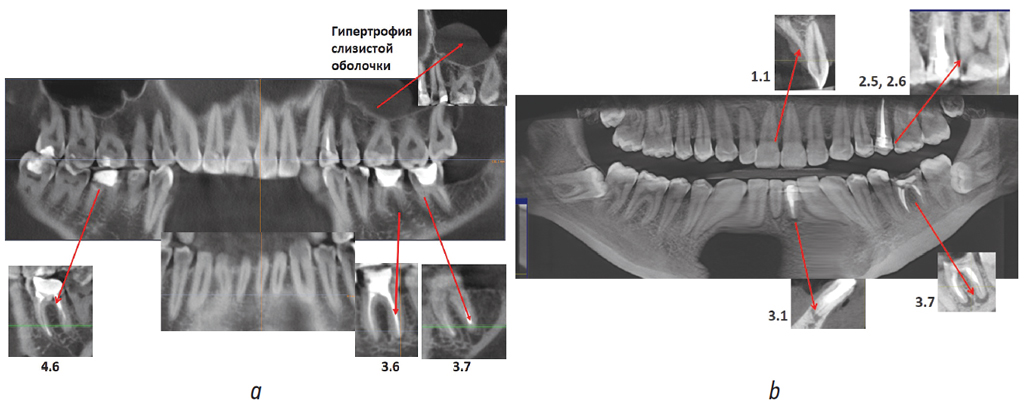

На рис. 7 представлены выполненные с помощью конусно-лучевой компьютерной томографии (КЛКТ) срезы зубных рядов пациентов, анализ которых позволил выявить периапикальные очаги деструкции костной ткани в области отдельных зубов (а, b), гипертрофию слизистой оболочки верхнечелюстной пазухи (а), ретенцию нижних третьих моляров (b).

Рис. 7. Срезы конусно-лучевой компьютерной томографии пациента Ч. (а) и пациентки Ж. (b) до лечения: а — периапикальные очаги деструкции в области зубов 2.6, 3.7, 3.6, 4.6, гипертрофия слизистой оболочки верхнечелюстной пазухи слева; b — очаги деструкции костной ткани в области корней зубов 3.6, 3.1, ретенция зубов 3.8, 4.8

Fig. 7. Cone-beam computed tomography slices of patient Ch. (a) and patient Zh. (b) before treatment: (a) periapical foci of destruction in the area of teeth 2.6, 3.7, 3.6, and 4.6, hypertrophy of the maxillary sinus mucosa on the left; (b) foci of bone destruction in the area of the roots of teeth 3.6 and 3.1, and retention of teeth 3.8 and 4.8